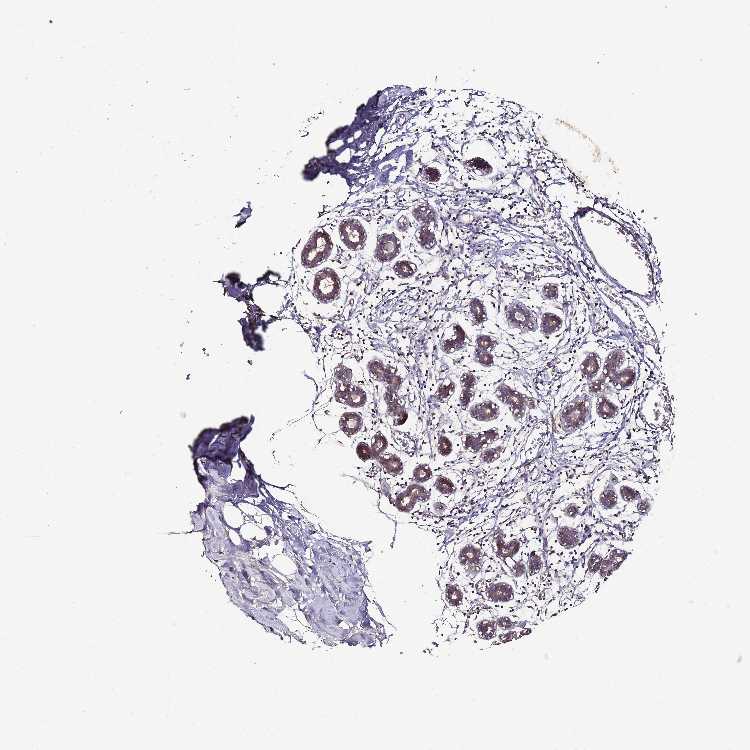

BREAST - Antibody stainingi

Antibody staining in the annotated cell types in the current human tissue is reported as not detected, low, medium, or high, based on conventional immunohistochemistry profiling in selected tissues. This score is based on the combination of the staining intensity and fraction of stained cells.

Each image is clickable and will lead to virtual microscopy that enables deeper exploration of all samples and also displays staining intensity scores, fraction scores and subcellular localization as well as patient and tissue information for each sample.

Antibody HPA042116Antibody HPA043556

Adipocytes Not detectedNot detected

Glandular cells LowMedium

Myoepithelial cells Not detectedNot detected